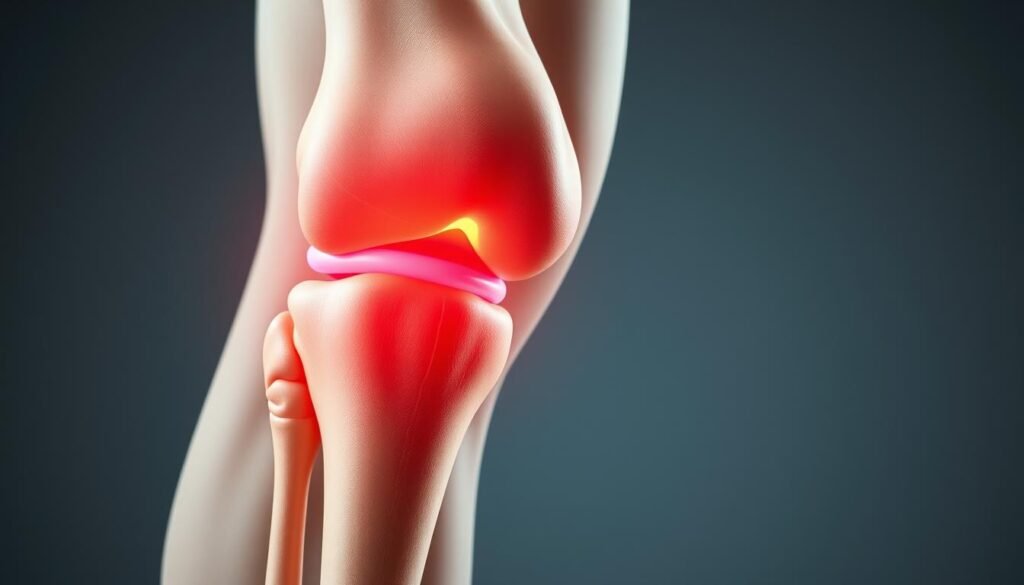

A dor no joelho ao subir escadas afeta muitas pessoas, independentemente da idade. Mas, para quem está mais velho, pode ser um sinal de artrose. A artrose, ou osteoartrite, é uma doença que degrada as articulações, como o joelho, causando dor e rigidez.

Quando a artrose ataca o joelho, a cartilagem que protege a articulação começa a desgastar-se. Isso pode causar dor, principalmente ao fazer esforço, como subir escadas. Além da dor, a artrose pode causar rigidez pela manhã, inchaço e uma sensação de ranger ao se mover.

Sintomas de Artrose no Joelho

A artrite no joelho, também chamada de osteoartrite, pode causar várias dores. Essas dores aparecem ao subir escadas e podem piorar com o tempo. Elas afetam cada pessoa de forma diferente.

Uma das principais dores é a rigidez ao acordar ou ficar parado por um tempo. Essa rigidez pode durar minutos ou horas. Isso torna difícil mover o joelho.

Outro sintoma comum é o inchaço ao redor do joelho. Esse inchaço acontece quando o líquido sinovial, que lubrifica a articulação, se acumula. Isso ocorre devido à inflamação da osteoartrite.

Além disso, a crepitação é um som de rangido ou estalido ao se mover. Esse som vem do atrito entre as superfícies ósseas, devido ao desgaste da cartilagem.

À medida que a osteoartrite avança, o movimento do joelho fica mais limitado. Isso dificulta fazer atividades simples, como agachar ou caminhar. Em casos graves, a dor no joelho pode ser muito forte, mesmo quando você está parado.